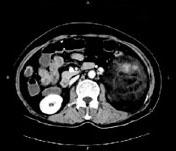

问题 女,64岁,左侧腰部胀痛,行CT扫描,下列说法正确的是 ( )

选项 A、考虑为左侧肾上腺来源的髓样脂肪瘤 B、考虑为腹膜后来源的脂肪肉瘤 C、该病灶密度不均匀,其内可见脂肪密度影,且呈不均匀强化 D、考虑为左肾来源的血管平滑肌脂肪瘤 E、左肾区可见一巨大的占位性病灶,境界较清楚,胰腺尾部受压向前推移

答案 CDE